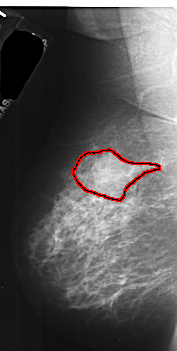

A_1036_1.LEFT_MLO

LEFT_MLO LINES 5251 PIXELS_PER_LINE 2641 BITS_PER_PIXEL 16 RESOLUTION 42 OVERLAY

FILE: A_1036_1.LEFT_MLO.OVERLAY

TOTAL_ABNORMALITIES 1

ABNORMALITY 1

LESION_TYPE MASS SHAPE IRREGULAR MARGINS ILL_DEFINED

ASSESSMENT 4

SUBTLETY 5

PATHOLOGY MALIGNANT

TOTAL_OUTLINES 1

BOUNDARY